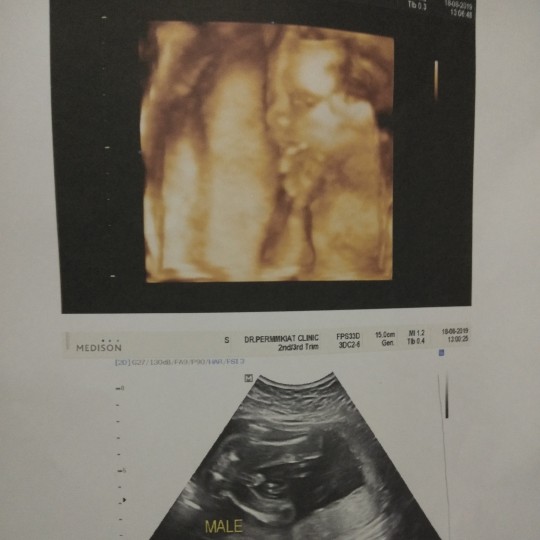

ซาวด์ตอน5เดือนค่ะ

ปากนิดจมูกหน่อย😁